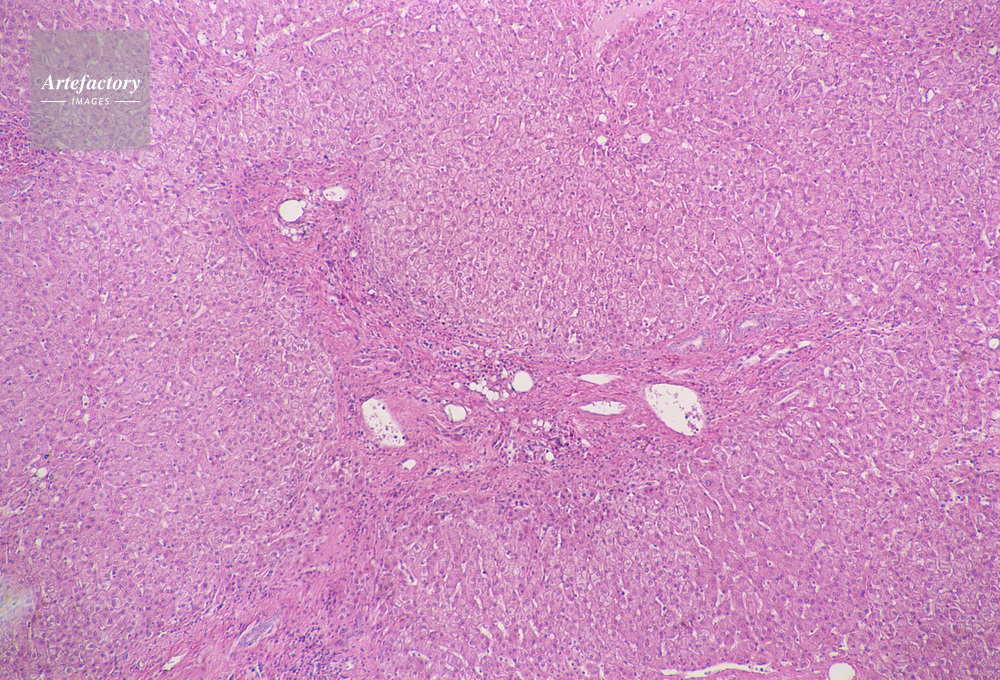

| 作品タイトル | 顕微鏡写真 | モデルリリース | なし | |

| キャプション | 人,ヒト,人物,肝臓 | 制限事項 | ||